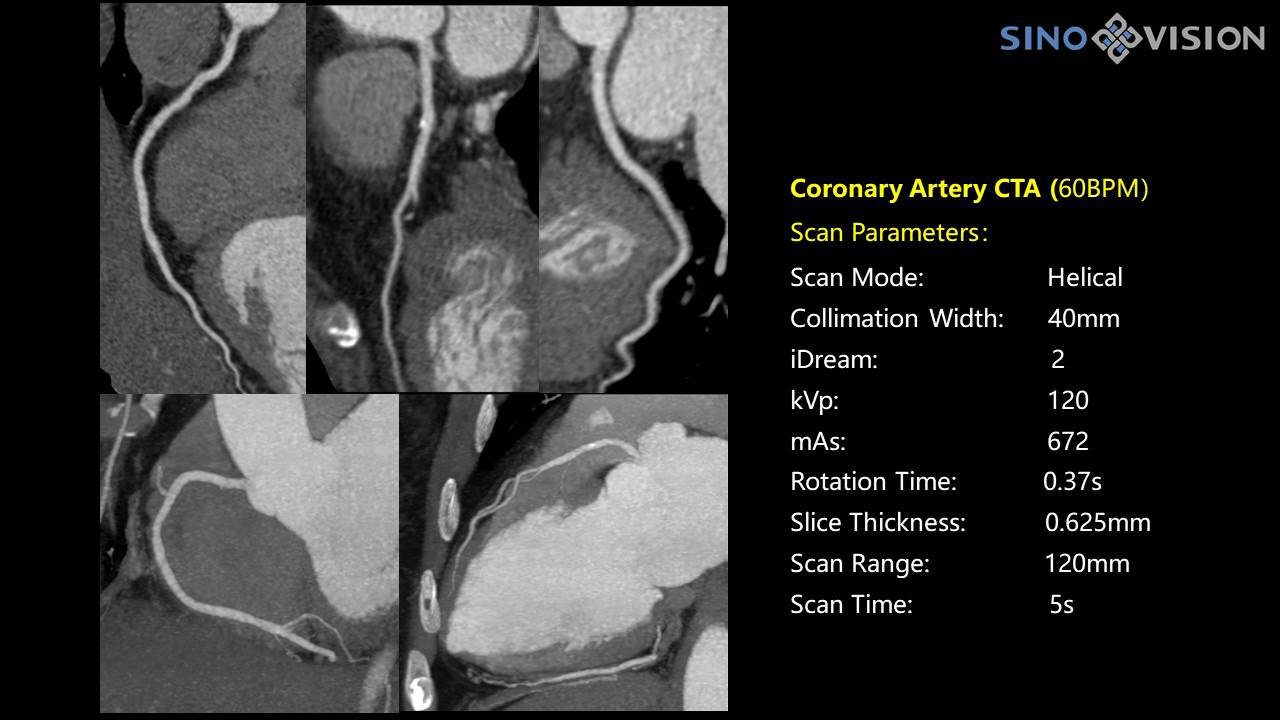

Специализированная технология RTF позволяет уменьшать артефакты движения сердца, обеспечивая максимально точное клиническое изображение.

- Коронарный анализ

- Ретроспективный режим сканирования с ЭКГ-синхронизацией

- Проспективный режим сканирования с ЭКГ-синхронизацией

- Режим последовательного сканирования c ЭКГ-синхронизацией и без ЭКГ-синхронизации

- Минимальное время одного оборота рентгеновской трубки: От 0.37 до 2 сек